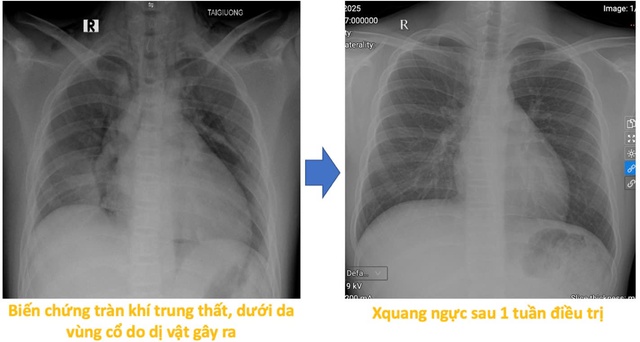

Hình ảnh Xquang tiến triển của bệnh nhi sau 1 tuần điều trị.

Sau thủ thuật, bệnh nhi giảm ho nhiều, đỡ khó thở và còn tức ngực nhẹ, song vẫn phải theo dõi do có biến chứng tràn khí trung thất và tràn khí dưới da vùng cổ. Hiện tại sức khỏe của bệnh nhi đã ổn định, các triệu chứng cũng tiến triển tốt và vẫn đang được điều trị theo phác đồ nội khoa sau hít phải dị vật.